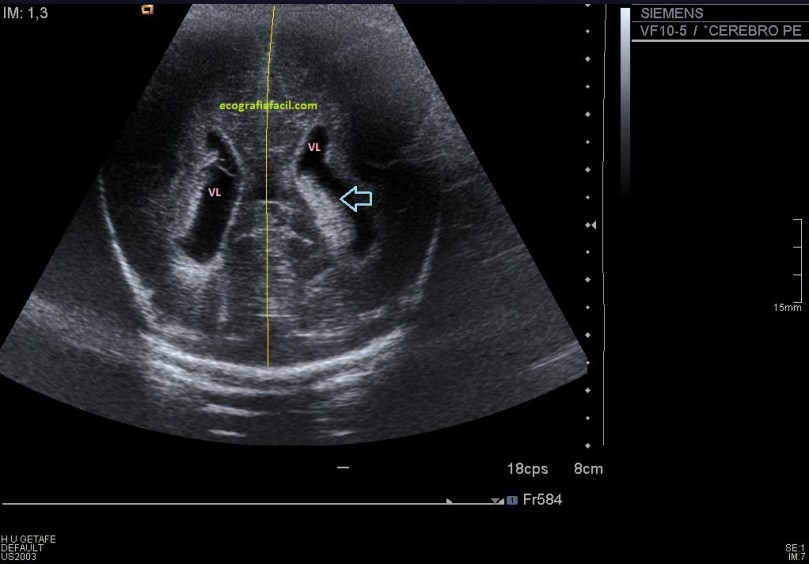

finalmente usamos una aplicación ya estudiada en el blog, como es la Panoramic View, donde podemos darle una visión global a la radióloga, donde podemos llegar a alcanzar medidas de estudio de 15 centímetros, como en este caso, cuando la medida de la huella de la sonda no supera los 5 centímetros. Visualmente es una imagen muy plástica, que ofrece a la radióloga una información no sólo de la lesión, sino también de la relación anatómica de la ecoestructura patológica con el tejido adyacente, ya sea normal o patológico.

En este caso en una misma imagen tenemos dos ecoestructuras patológicas, la masa o el tumor y la lesión vascular de los vasos, también con ecoarquitecturas normales como la del testículo anteriormente explicado.

Esta imagen es muy bonita por que puedes ver como el canal inguinal se abre para albergar a la masa, en el cordón y como a continuación el varicocele.